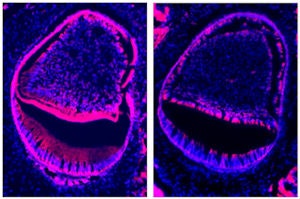

| In a normal mouse tooth (left), ameloblast cells that produce tooth enamel glow in red. In a tooth with the Ctip2 gene deleted (right), little enamel has been able to form. Image courtesy of Oregon State University. |

The researchers used a laboratory mouse model in which the Ctip2 gene has been removed and its protein is missing. Such mice lack basic biological systems and cannot live after birth, but allow scientists to study what is there and what's missing, Kioussi noted. In this case, the mice had rudimentary teeth ready to erupt, but they lacked a proper enamel coating and never would have been functional.